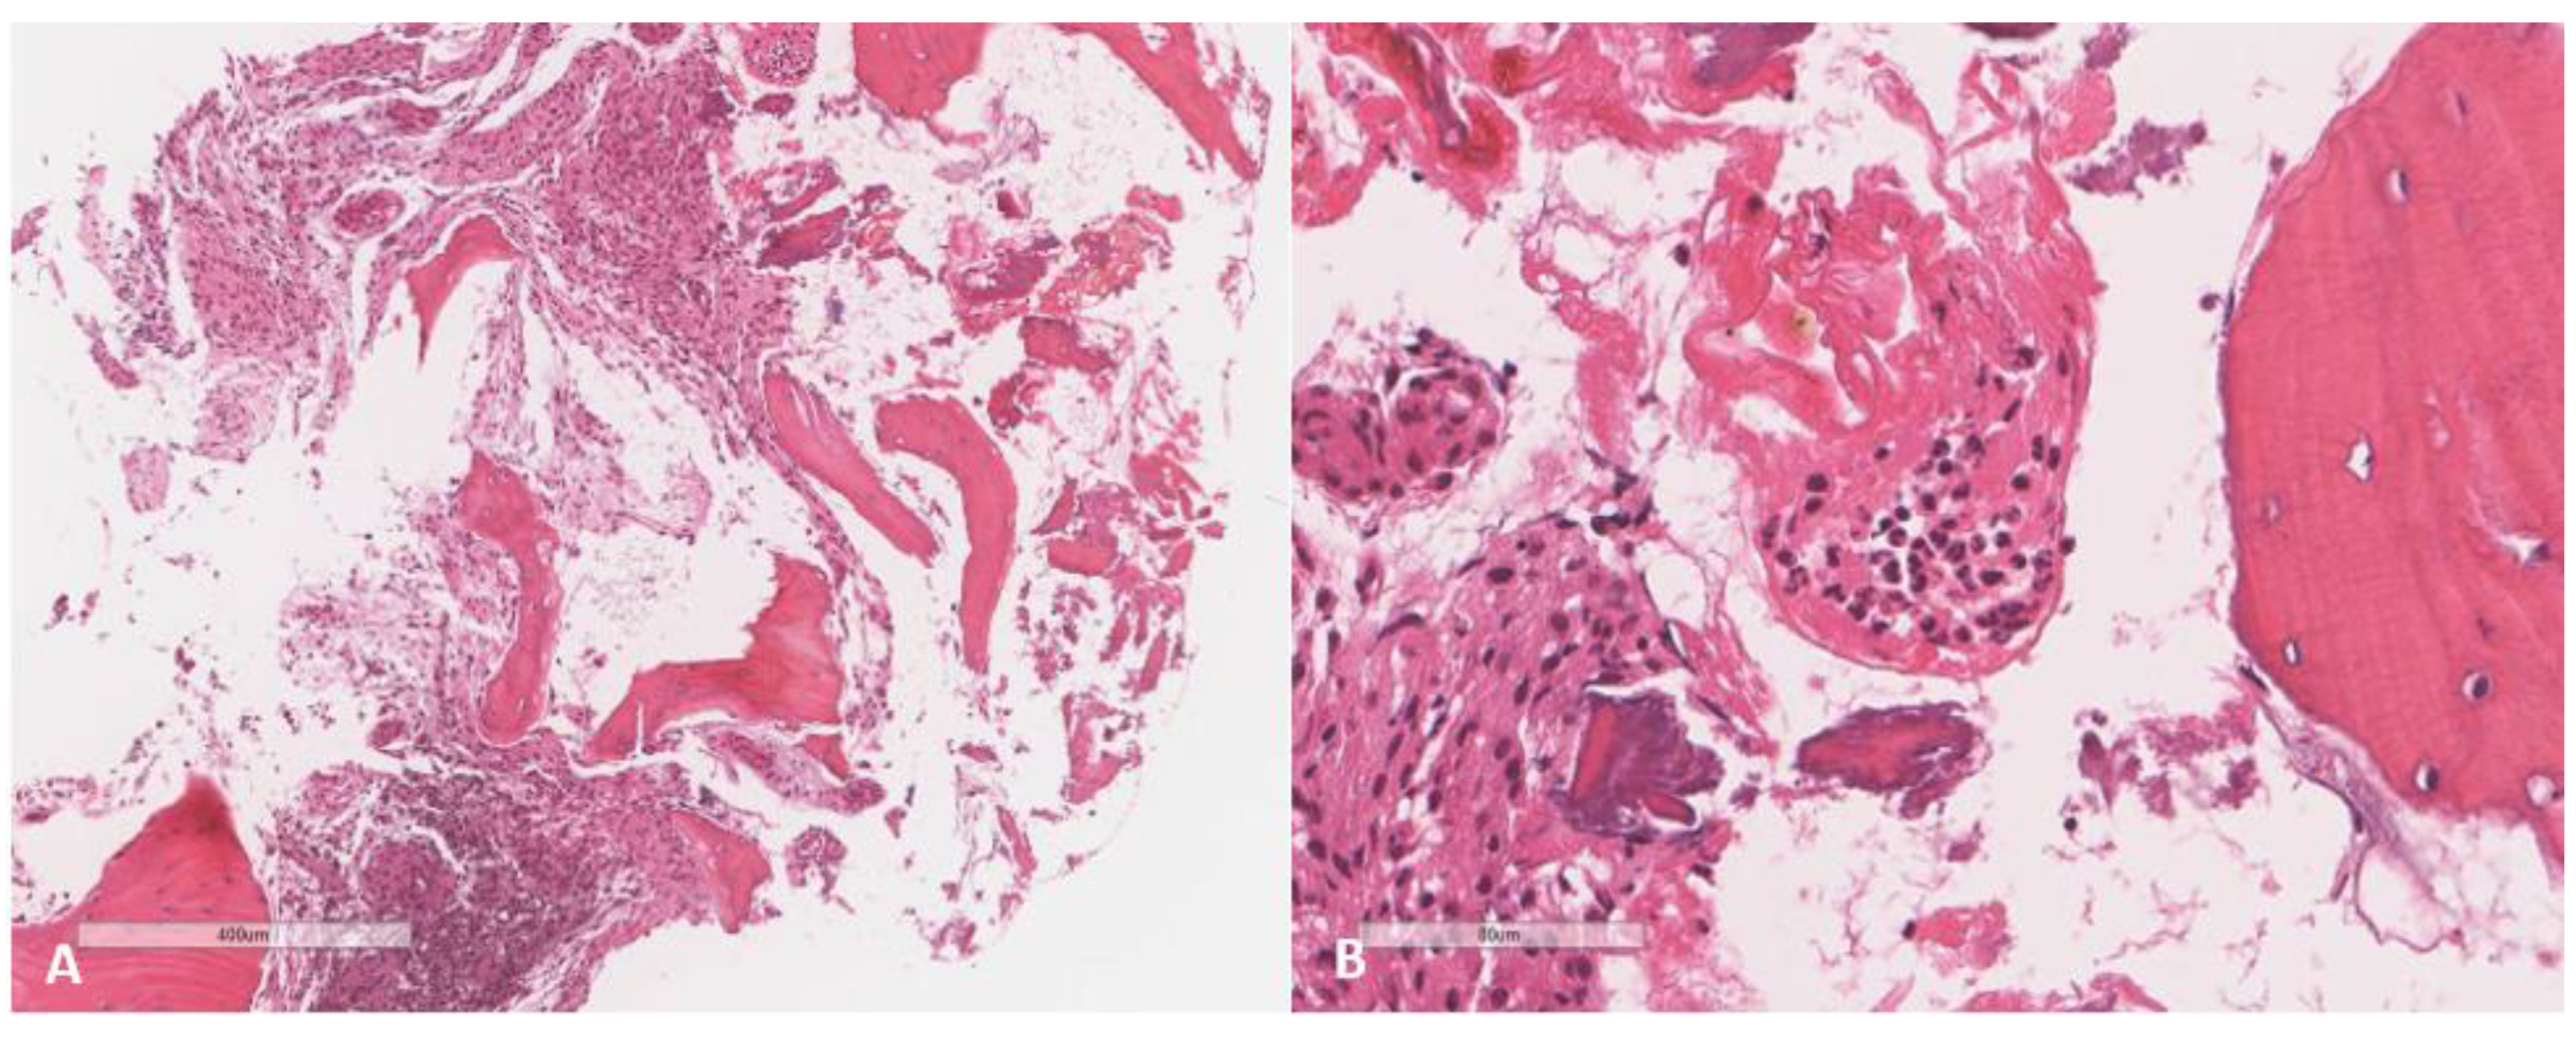

2. Case

| Index case | 12Y/F | Healthy child | Chronic osteomyelitis | Tissue culture | P. species | VRC total 6 months with surgical debridement | Resolution |